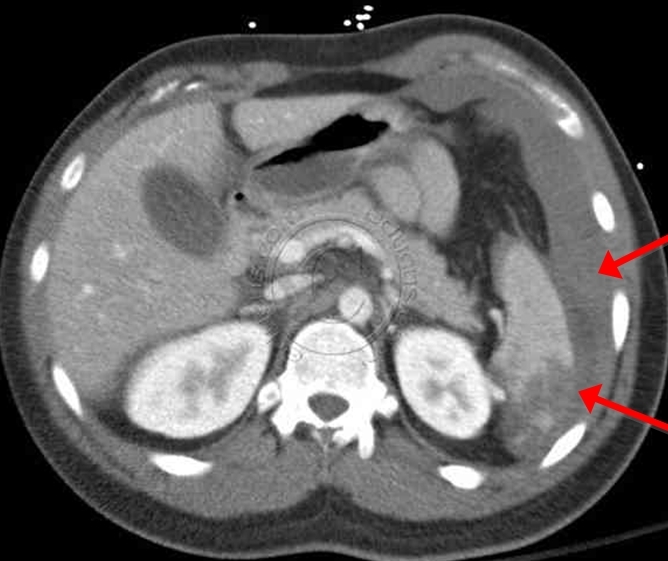

Blunt Trauma

Focused abdominal sonography for trauma (FAST) scan can be used to evaluate potential areas of blood collection within the peritoneum. It should be the first step in alert and hemodynamically stable (eg, systolic blood pressure >90 mm Hg) patients. If FAST is limited or equivocal, a diagnostic peritoneal lavage (DPL) can be done to evaluate for hemoperitoneum, but only for blunt and not penetrating trauma. Hemodynamically unstable patients with a positive finding on either DPL or FAST should undergo exploratory laparotomy. Hemodynamically stable but altered should undergo CT.

CT scan of the abdomen gives detailed information about the pathology and source of hemorrhage (if present). It may also assist in planning of operative intervention.